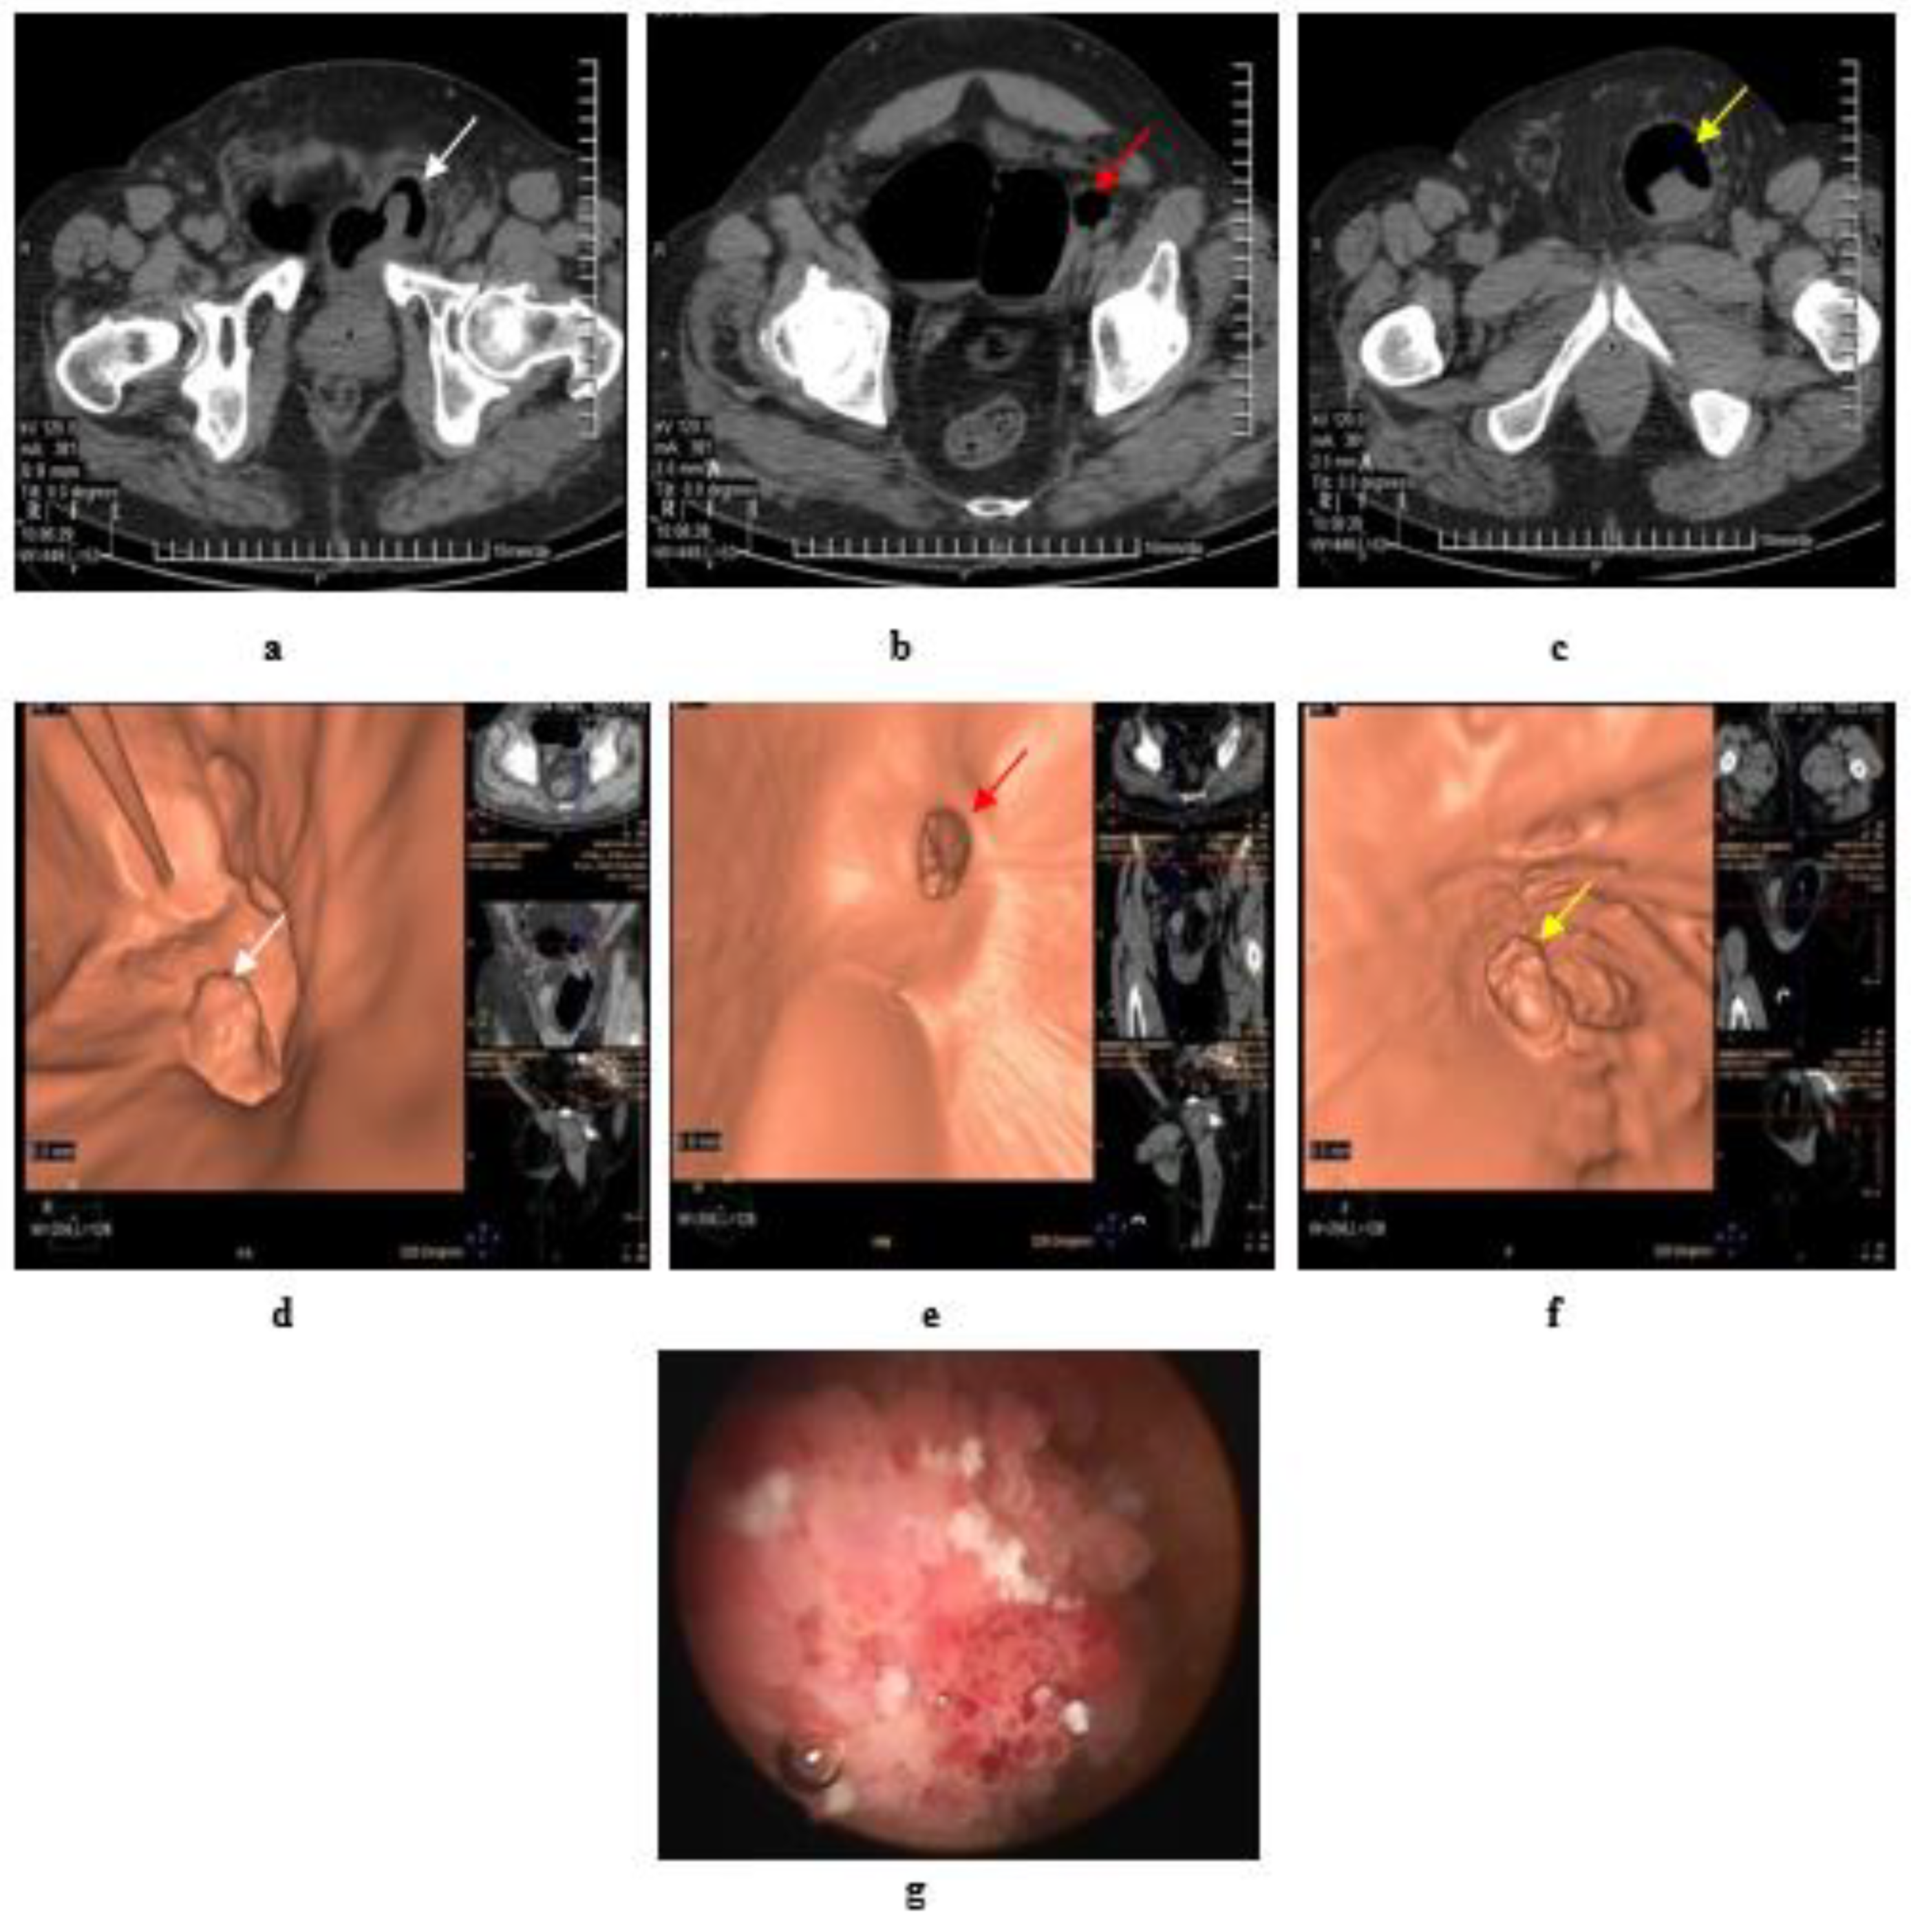

2.5. Virtual Cystoscopy (VC)

- Noncontrast CT of the pelvis subsequent to air/CO2 filling via a urethral catheter, then virtual reconstruction of images.

- Delayed phase of MDCT urography, then CT virtual cystoscopy reconstruction.